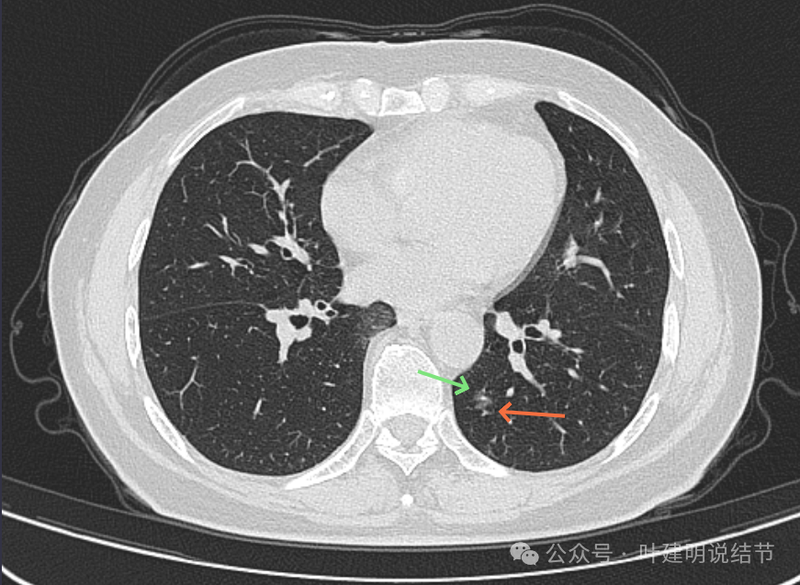

病灶出现,磨玻璃密度,略有偏实性成分,整体轮廓与边界较为清楚。

混合密度,轮廓清。有实性成分、有局部细支气管扩张、有浅分叶征,病灶有明显磨玻璃成分。

灶内细支气管扩张、边缘毛刺、虽小却有明显分叶征、整体轮廓与边界清楚、实性成分明显。

细支气管扩张以及边缘细毛刺,整体轮廓清。

磨玻璃密度伴少许偏实性成分,有微小血管进入。

边缘区密度淡,但轮廓仍清。